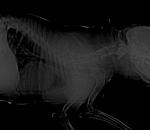

Снимки хорошие, качественные, но совершенно не информативные. На этих пленках патология не определяется. Но здесь нет снимка, который нужен обязательно - поясничный отдел позвоночника в прямой проекции (такой, как 3-й, но только не шея, а поясница).

Нет,наоборот.Собака сначала стала немного наклонять голову вправо.Когда были на консультации у окулиста,то он обратил внимание на это ,сказал,что есть какие-то изменения в области шеи.Я отсутствовала дома 2 недели.Приехала,собаку вообще не узнала.Крен головы вправо стал еще сильнее,передние ноги как-то ослабли.Она идет,может споткнуться,упасть.Сходили,сделали рентген.снимок.Поставили диагноз:атланто-аксиальная нестабильность шейного отдела,спондилоартроз. Проколола 5 дней:актовегин,папаверин,комбилипн,мидокалм,дексаметазон. Пока делала уколы и еще дней 5 после этого собаке стало легче,а потом опять вернулись к тому, что было.На консультации врач сказал,что дальше просто колоть преднизалон. Я уехала к другому врачу,тот сделал снимки,которые я Вам отослала.Сказал, что диагноз не подтверждает,на пальцах показал, что со спинным мозгом все нормально.С помощью какой-то процедуры (бумаги на работе)обнаружил перфорацию барабанной перепонки.Выписал лечение:цефтриаксон,циклоферон,цебролизин(колола 2 дня,стало хуже),комбилипен.В уши-изотик.Сказал,что может быть у собаки был инсульт.Собаке от лечения хуже.Вот такие дела.

Непростая у вас ситуация. Получается, диагноза пока нет, поэтому и лечить эффективно не получается.